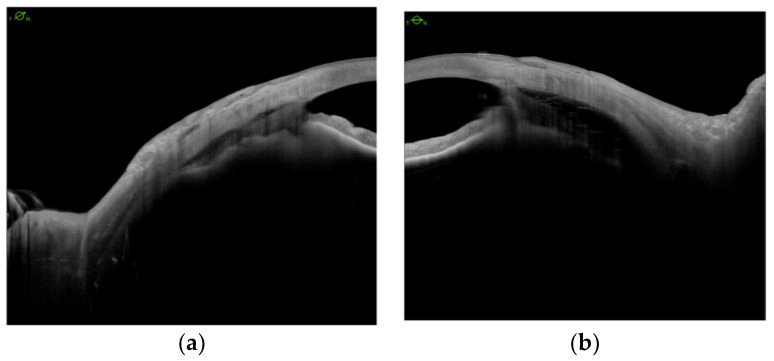

We analyzed CBD before and after scleral buckling surgery (Figure 3a,b), and no eye showed any significant changes postoperatively (Figure 3c,d).

Next, we analyzed the effect of surgery on IOP and BCVA. The mean IOP increased in all eyes (4.83 mmHg preoperatively, Me = 4.50; SD = 0.98 vs. 10.17 mmHg postoperatively, M = 10.17, Me = 9.50; SD = 3.37; p = 0.006), with subsequent improvement in best-corrected visual acuity (1.91 logMAR preoperatively, Me = 2.28, SD = 0.59, vs. 1.50 postoperatively, Me = 1.41, SD = 0.59; p = 0.034) (Table 1).